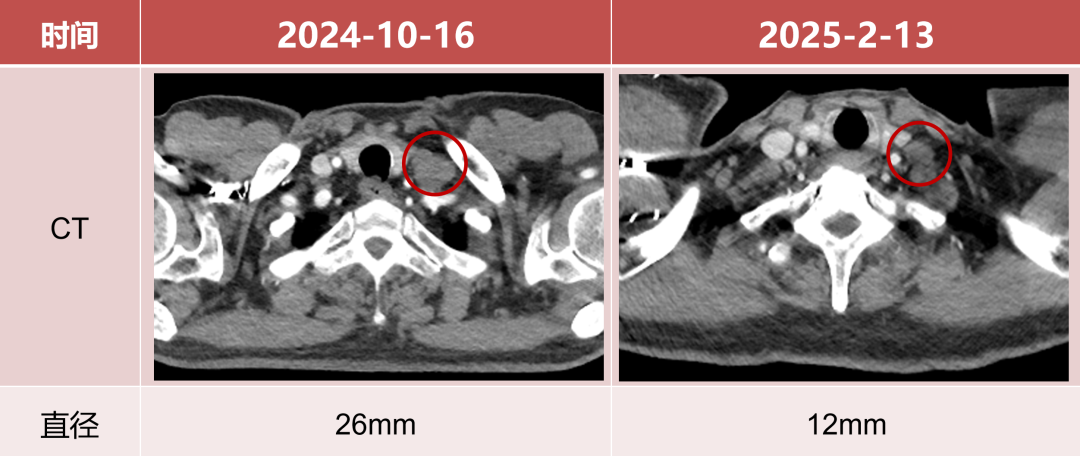

用药16周后淋巴结评估

• 左髂血管旁淋巴结直径较前减小70%。

图片9.png

• 左锁骨下淋巴结直径较前减小53.8%。

图片10.png